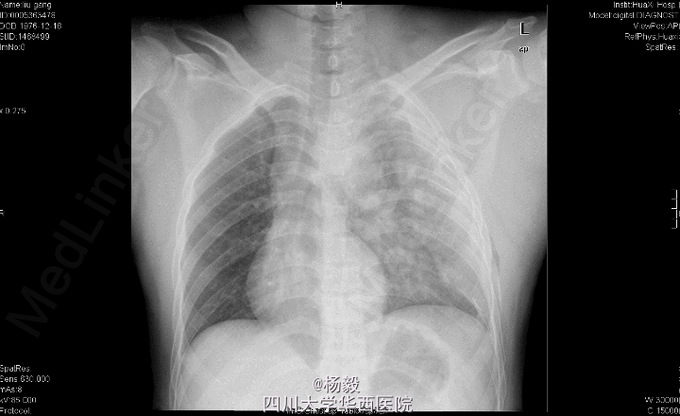

男,33岁11月,因“车祸伤后全身多处疼痛、左上肢活动障碍9小时”入院。 患者自述入院前9小时,被货车撞伤,具体受伤姿势及着力方式不清,患者原发昏迷约5分钟,醒后能回忆受伤情况,患者述胸部及左肩部疼痛,呼吸困难,气促,左上肢感觉麻木,左手伸屈活动受限,患者无恶心呕吐,无咯血,感腹部稍微疼痛,无大小便失禁,其余四肢无活动障碍,曾经当地医院诊治,具体诊断不详,行对症治疗后,患者感呼吸困难加重,为进一步治疗,患者转我院,门诊请胸科会诊后行左侧胸腔闭式引流术,请普外科会诊后,认为腹部无明显指征,暂观察,急诊以“左肩胛骨骨折,左肱骨外科颈骨折,胸腔积液'收住我科。

胸廓左侧胸廓呼吸动度减弱,左胸部腋中线处见一闭式引流管接水封瓶。,双肺叩诊呈清音,双肺呼吸音清,未闻及干湿啰音及胸膜摩擦音。腹部外形正常,全腹柔软,上腹压痛,无反跳痛,腹部未触及包块,肝脏肋下未触及,脾脏肋下未触及,双肾未触及。双下肢无水肿。专科检查:视:左上臂夹板外固定,解开夹板后见左肩部及左上臂肿胀,左上臂下段外侧见约5cm*8cm皮肤擦伤。触:左肩胛部及左肩部压痛,左前臂下段 以远痛温触觉较对侧减退,左桡动脉能扪及,左手甲床微循环正常。动量:左肩关节、左肘关节、左腕关节及左手指各关节伸屈活动受限。 辅助检查:X片检查示:左肩胛骨及左肱骨上段骨折,左侧多发肋骨骨折,左肺挫伤,左胸腔积液,脾区高密度影。

初步诊断:1、左肩胛骨粉碎性骨折。2、左肱骨外科颈骨折伴神经损伤。3、左侧胸腔积液闭式引流术后。4、左侧多发肋骨骨折。5、左肺挫伤。6、脾脾脏损伤? 全麻下行左肱骨外科颈骨折切开复位内固定术。